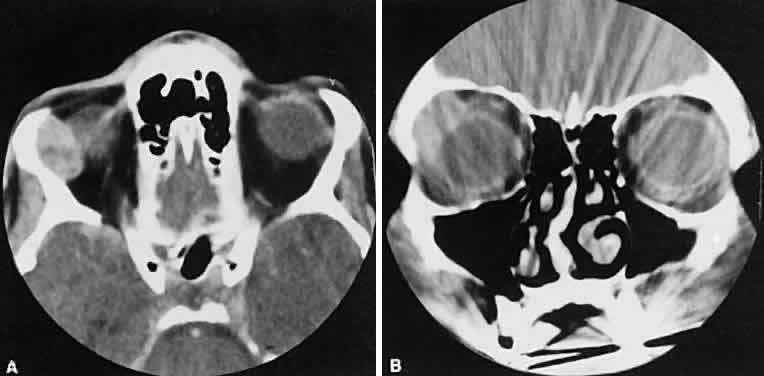

The muscle belly has a smooth contour with no edema of the adjacent orbital fat. We recently evaluated a patient with a referral diagnosis of Graves' orbitopathy. The patient was euthyroid but had severe orbital congestion typical of advanced Graves' orbitopathy. Imaging showed “dirty” orbital fat and lateral rectus muscle morphology that seemed atypical (Fig. 8). Biopsy specimen results showed a low-grade lymphoma. Hypertrophy of the medial rectus muscle can cause the medial wall to bow in toward the ethmoidal sinus from the chronic effects of pressure on the bone. The hypertrophied muscles also can give rise to a compressive optic neuropathy in the orbital apex as the enlarged muscles take their origin from the anulus of Zinn. Axial views of the apex show an apparent mass if the inferior rectus muscle is enlarged. It is imperative that additional views, sagittal or preferably coronal, be obtained to show the true nature of this apparent mass. Intracranial fat prolapse, seen by CT, may be another sign of optic neuropathy.44 An optic neuropathy also can be seen with relatively normal-sized EOM. An expanded fat compartment with optic nerve stretch has been associated with an optic neuropathy.45,46

Fig. 8. Low-grade lymphoma confined to orbit mistaken for Graves' ophthalmopathy in a 65-year-old man. A. On the axial view, orbital fat appears “dirty” with marked increase in soft tissue stranding. Muscles do not have a smooth appearance, lateral rectus muscles have lumpy appearance (arrow), and both lateral rectus muscles are disproportionately large for what typically is seen in Graves' orbitopathy. B. Coronal view also shows dirty orbital fat. Note left inferior rectus, which is small (arrowhead), and also is atypical in Graves' orbitopathy when there is enlargement of the other extraocular muscles.